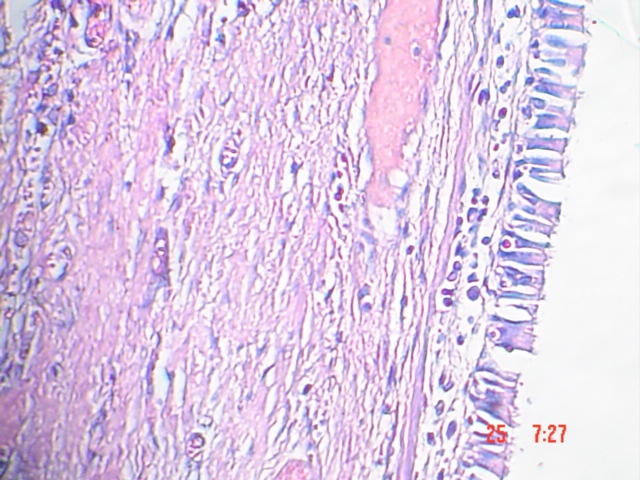

- <div style=fiogf49gjkf0d Fig. 6-7 Se observa hacia uno de los extremos epitelio cilíndrico ciliado de tipo respiratorio, subyacente al cual apreciamos tejido conectivo vascularizado con infiltrado inflamatorio y parénquima pulmonar. H-E 100X">

Fig. 6-7 Se observa hacia uno de los extremos epitelio cilíndrico ciliado de tipo respiratorio, subyacente al cual apreciamos tejido conectivo vascularizado con infiltrado inflamatorio y parénquima pulmonar. H-E 100X

- <div style=fiogf49gjkf0dFig. 8. A mayor aumento se aprecia el epitelio de tipo respiratorio (cilíndrico pseudoestratificado ciliado con células caliciformes). H-E 400X">

Fig. 8. A mayor aumento se aprecia el epitelio de tipo respiratorio (cilíndrico pseudoestratificado ciliado con células caliciformes). H-E 400X